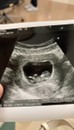

น้อง10วีค3วันค่ะ

น้องยาวได้ 3.6ซ.ม.